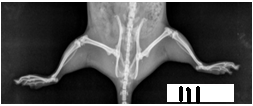

Photographs. 1, 2, 3 are of Anti-arthritic activity of Effect of Petroleum ether and Methanol extract of leaf of Pergularia daemia [Forsk]

Radiographic Analysis

On the 21st day immediately after measurement of paw volume displacement and recording of secondary lesions, the one rat from each group was animals were sacrificed by cervical dislocation and carotid bleeding and subjected to the radiological examination using Agfa digital System and Seimens X ray machine. These radiographs were evaluated for any deformity especially for soft tissue swelling and bone erosion, joint space narrowing by independent qualified person. [21]

Radiographic analysis is considered to be the best tool to screen the any drug in this regard. In present study radiographic analysis of the joint showed significant prevention in progress of joint [20, 21]. By synthetic therapy, there is rapid reduction in inflammation in arthritis is observed with corticosteroids but the effect of these drugs were for short time. Corticosteroids become less effective over time where as arthritis is usually active for years together [22]. From the above research work, the leaf extract of Pergularia daemia [Forsk] is a good substitute for corticosteroids therapy for arthritis.